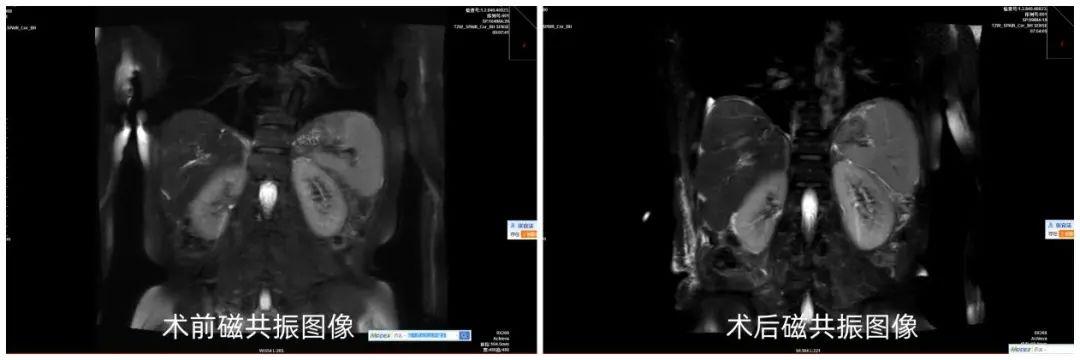

一、中西合璧攻克胆管结石顽疾

自年轻时起,张女士便与胆总管及肝内胆管结石如影随形,四十余年间先后接受过四次胆道取石手术包括胆肠吻合手术治疗,但未能彻底治愈,长期受腹痛折磨。辗转来到六安市中医院,肝胆胰专家团队经过慎重术前讨论,对病情进行深入评估,决定采用“左肝联合全尾状叶切除+肝内胆管切开取石+胆总管探查胆道镜取石+T管引流术”,并制定了详细的手术预案,手术历时4个多小时顺利完成。术后恢复良好,复查肝功能正常,磁共振提示无肝胆管结石残留。

同时,面对多次取石后结石复发率高的问题,专家团队充分发挥中医中药在“从肝治胆”上的优势,为患者制定了个性化的疏肝利胆预防结石复发方案,力求从源头上斩断结石“卷土重来” 的可能。